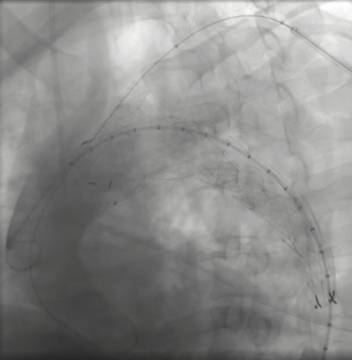

Aortography revealed a descending thoracic aortic dissection with an entry tear just distal to the left subclavian artery. Through right femoral access, a SEAL thoracic stent graft (38¡¿150 mm) was deployed across the rupture site. A Bentley BeGraft chimney stent (10¡¿57 mm) was placed via left brachial access to preserve subclavian perfusion. Final angiography confirmed proper stent apposition and complete exclusion of the rupture without endoleak.

Following stabilization, a dual-access endovascular approach was performed under general anesthesia with ultrasound-guided puncture of the right femoral (22 Fr, pre-closed with two Proglides) and left brachial (7 Fr) arteries. After systemic heparinization (5,000 IU), aortography delineated an entry tear distal to the left subclavian artery. A SEAL Thoracic Stent Graft (38 ¡¿ 150 mm) was precisely deployed across the rupture site, and a Bentley BeGraft Chimney Stent (10 ¡¿ 57 mm) was inserted via the brachial route to maintain left subclavian perfusion. Completion angiography confirmed optimal stent apposition and full exclusion of the pseudoaneurysm without endoleak. Hemodynamics remained stable throughout, and MAP was maintained at 80 mmHg for 48 hours post-procedure. The intervention achieved complete sealing with no complications.